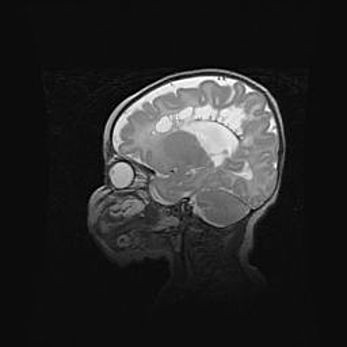

Мальформация Денди-Уокера. Киста задней черепной ямки.

Агенезия мозолистого тела.

Возраст: 2,5 месяца

Вес: 2420 г

Пол: женский

Окружность головы: 37 см

Срок гестации: 32 недели

Мальформация Денди—Уокера — редкий вид патологии ЦНС, представляющий собой врожденный порок развития каудального отдела ствола и червя мозжечка, ведущий к неполному раскрытию срединной (Мажанди) и латеральных (Лушка) апертур IV желудочка мозга. Для этогно синдрома характерна триада симптомов: гипотрофия червя мозжечка и/или полушарий мозжечка, кисты задней черепной ямки, гидроцефалия различной степени. В 70% случаев порок сочетается и с другими аномалиями головного мозга, в частности с агенезией мозолистого тела.